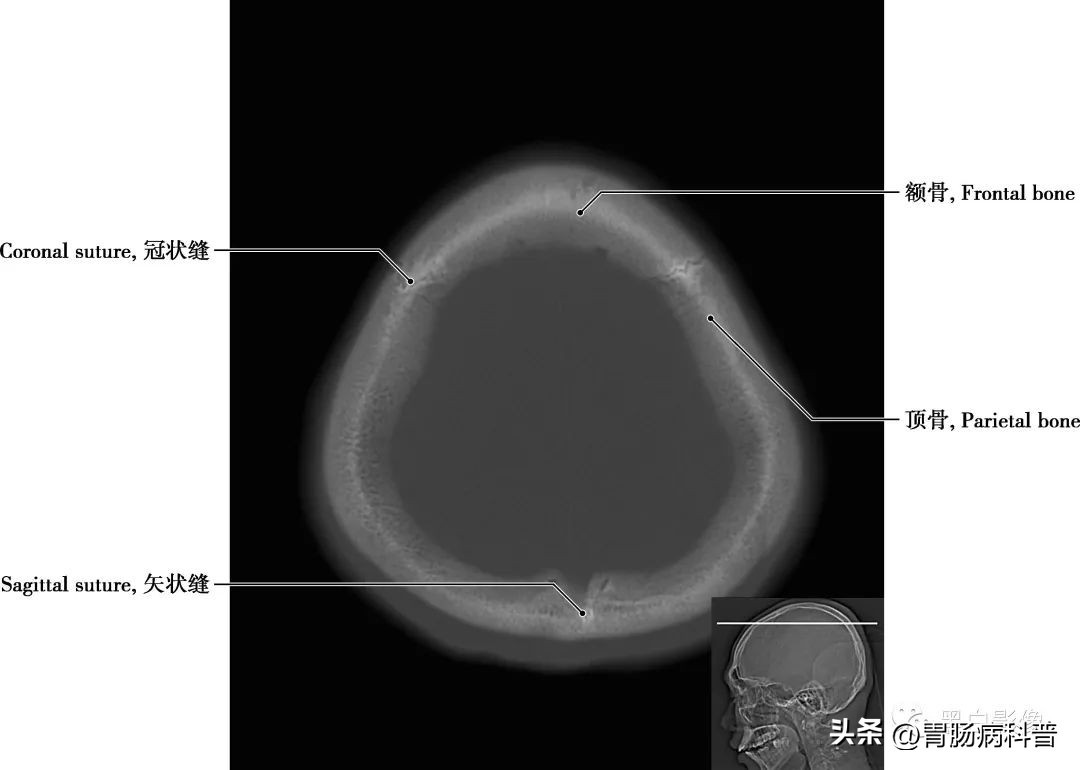

图1-2-1 经顶骨轴位切面

顶骨 位于颅盖的中部,左右各一,呈四边形,为外凸内凹典型的扁骨